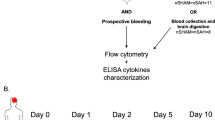

CD11b-HSVTK-mouse model with intraventricular application of ganciclovir

To evaluate the impact of microglia activation on secondary brain injury after experimental SAH, we used Nestin-GFP HSVTK-mice for our experiments. In these animals, Nestin-positive cells (e.g., neuronal precursors) are GFP-positive as well. To rule out a contribution of Nestin-positive cells to our cell counts of Iba-1- and NeuN-positive cells, unstained sections were evaluated for Nestin-GFP signal before further processing. No native Nestin-GFP signal was found in our mice.

CD11b-HSVTK mice have been described earlier [32]. In brief, CD11b-positive cells (e.g., monocytes, macrophages and microglia) harbor the HSVTK suicide gene, which is sensitive to ganciclovir. Application via an osmotic mini pump into the ventricular system targets intracerebral CD11b-positive cells (i.e., microglia) in the CNS predominantly similarly as described earlier [24, 69]. Experimental SAH was induced in CD11b-HSVTK mice as described above. Thereafter, animals were turned into a prone position, the scalp was incised, and a navigated burr hole craniotomy was established 0.8 mm parasagittal on the level of the bregma. Via this craniotomy the ventricular catheter of an osmotic mini pump (Alzet© Brain Infusion Kit, Charles River) filled with ganciclovir (2 mg/ml; 230 µl/pump) was introduced and connected proximally to the pump. Negative littermate CD11b-HSVTK mice served as controls.

After 9 days of infusion, the brains of these mice were harvested, cut in coronary slices (10 µm) and stained for Iba-1 and neuronal cell death, as described above.

Taken together we show that SAH in mice and humans leads to a secondary wave of intracerebral inflammation, mediated mainly via an accumulation of resident microglia cells, which coincided with a presumably secondary neuro-axonal injury. In order to further test the hypothesis, that the brain becomes a target of its own resident (microglia-based) immune system after SAH, i.e., that resident microglia mediate this neuro-axonal injury, we depleted microglia in vivo using CD11b HSVTK+/− mice [32]. Here, intraventricular infusion of ganciclovir, as also reported elsewhere [24, 69], leads to a substantial reduction of CD11b-positive cells (Fig. 6a), resulting in a decrease of microglia by 76 % compared to the CD11b HSVTK−/− littermate control animals (Fig. 6b).

Microglia induce neuronal apoptosis in experimental subarachnoid hemorrhage. a Illustration of the experimental protocol. Ganciclovir (GCV)-loaded minipumps were intraventricularly implanted to deplete microglia for 9 days in the animal model of Herpes simplex virus-thymidine kinase (TK+)—following SAH induction, as well as in their respective littermates (TK−). In the TK+ animals, all CD11b-positive cells harbor the thymidine kinase, which could be targeted by ganciclovir and leads to a depletion of the respective cells. Illustrative IF images show a significant reduction of Iba-1-positive cells in the depleted animals. b Through quantification of Iba-1-positive cells, a decline of about two-thirds could be documented at the time point of analysis. c Illustrative immunofluorescence staining of TK− (upper image) and TK+ animals (lower image). Scalebars = 100 µm. d In the non-depleted animals (TK−), a significant number of apoptotic neurons was detected on day 9 after induction of the hemorrhage, while in comparison, in TK+ animals the number of apoptotic neurons was significantly reduced. e Also the number of the survived neurons was significantly higher in TK+ (microglia-depleted) animals than in TK− (non-depleted) *p < 0.05, **p < 0.01, ***p < 0.001. t test, n = 4 per group

In order to address, whether microglia accumulation is cause or consequence of delayed neuronal injury after SAH, we found the number of dying neurons upon SAH in the microglia-depleted animals significantly reduced by two-thirds after SAH in comparison to their CD11b HSVTK−/− littermates with unaffected microglia (Fig. 6c, d). Accordingly, the number of residual, vital neurons was significantly higher in microglia-depleted animals (Fig. 6e).